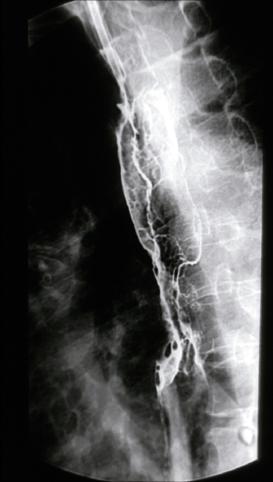

疾病(病理主体)的分类恶性上皮肿瘤/未分化癌

部位(按器官分)食道/2个以上

检查方法X线

肿瘤的肉眼分类5型(难以分类)/

肿瘤最大直径40以上

多发性肿瘤(同一器官)

多重性肿瘤(多个器官)